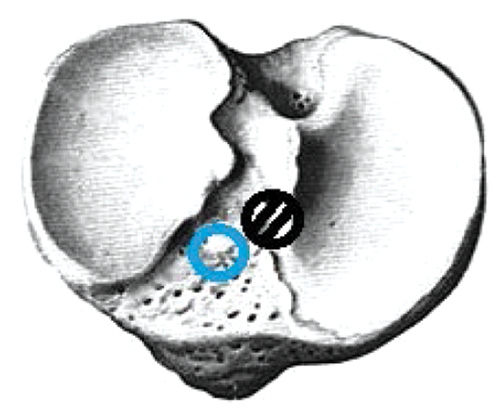

The actual revision surgery was similar to the primary ACL plastic surgery, and achieving the correct anatomical location of the channels was the focus. Since the landmarks were less clear than that in primary plastic surgery, the PCL attachment site was a landmark for the tibial channel location, and the new channel was tried to be placed in the middle and slightly medial to the intercondylar eminence. When the primary intraosseous channel was located outwardly in the tibia, we formed inwardly a new channel of a larger diameter and centered the graft in the channel using a BioIntrafix sleeve (DePuy Mitek, USA) (Fig. 1).

Fig. 1. The location of the primary tibial canal outward, — correct channel placement.